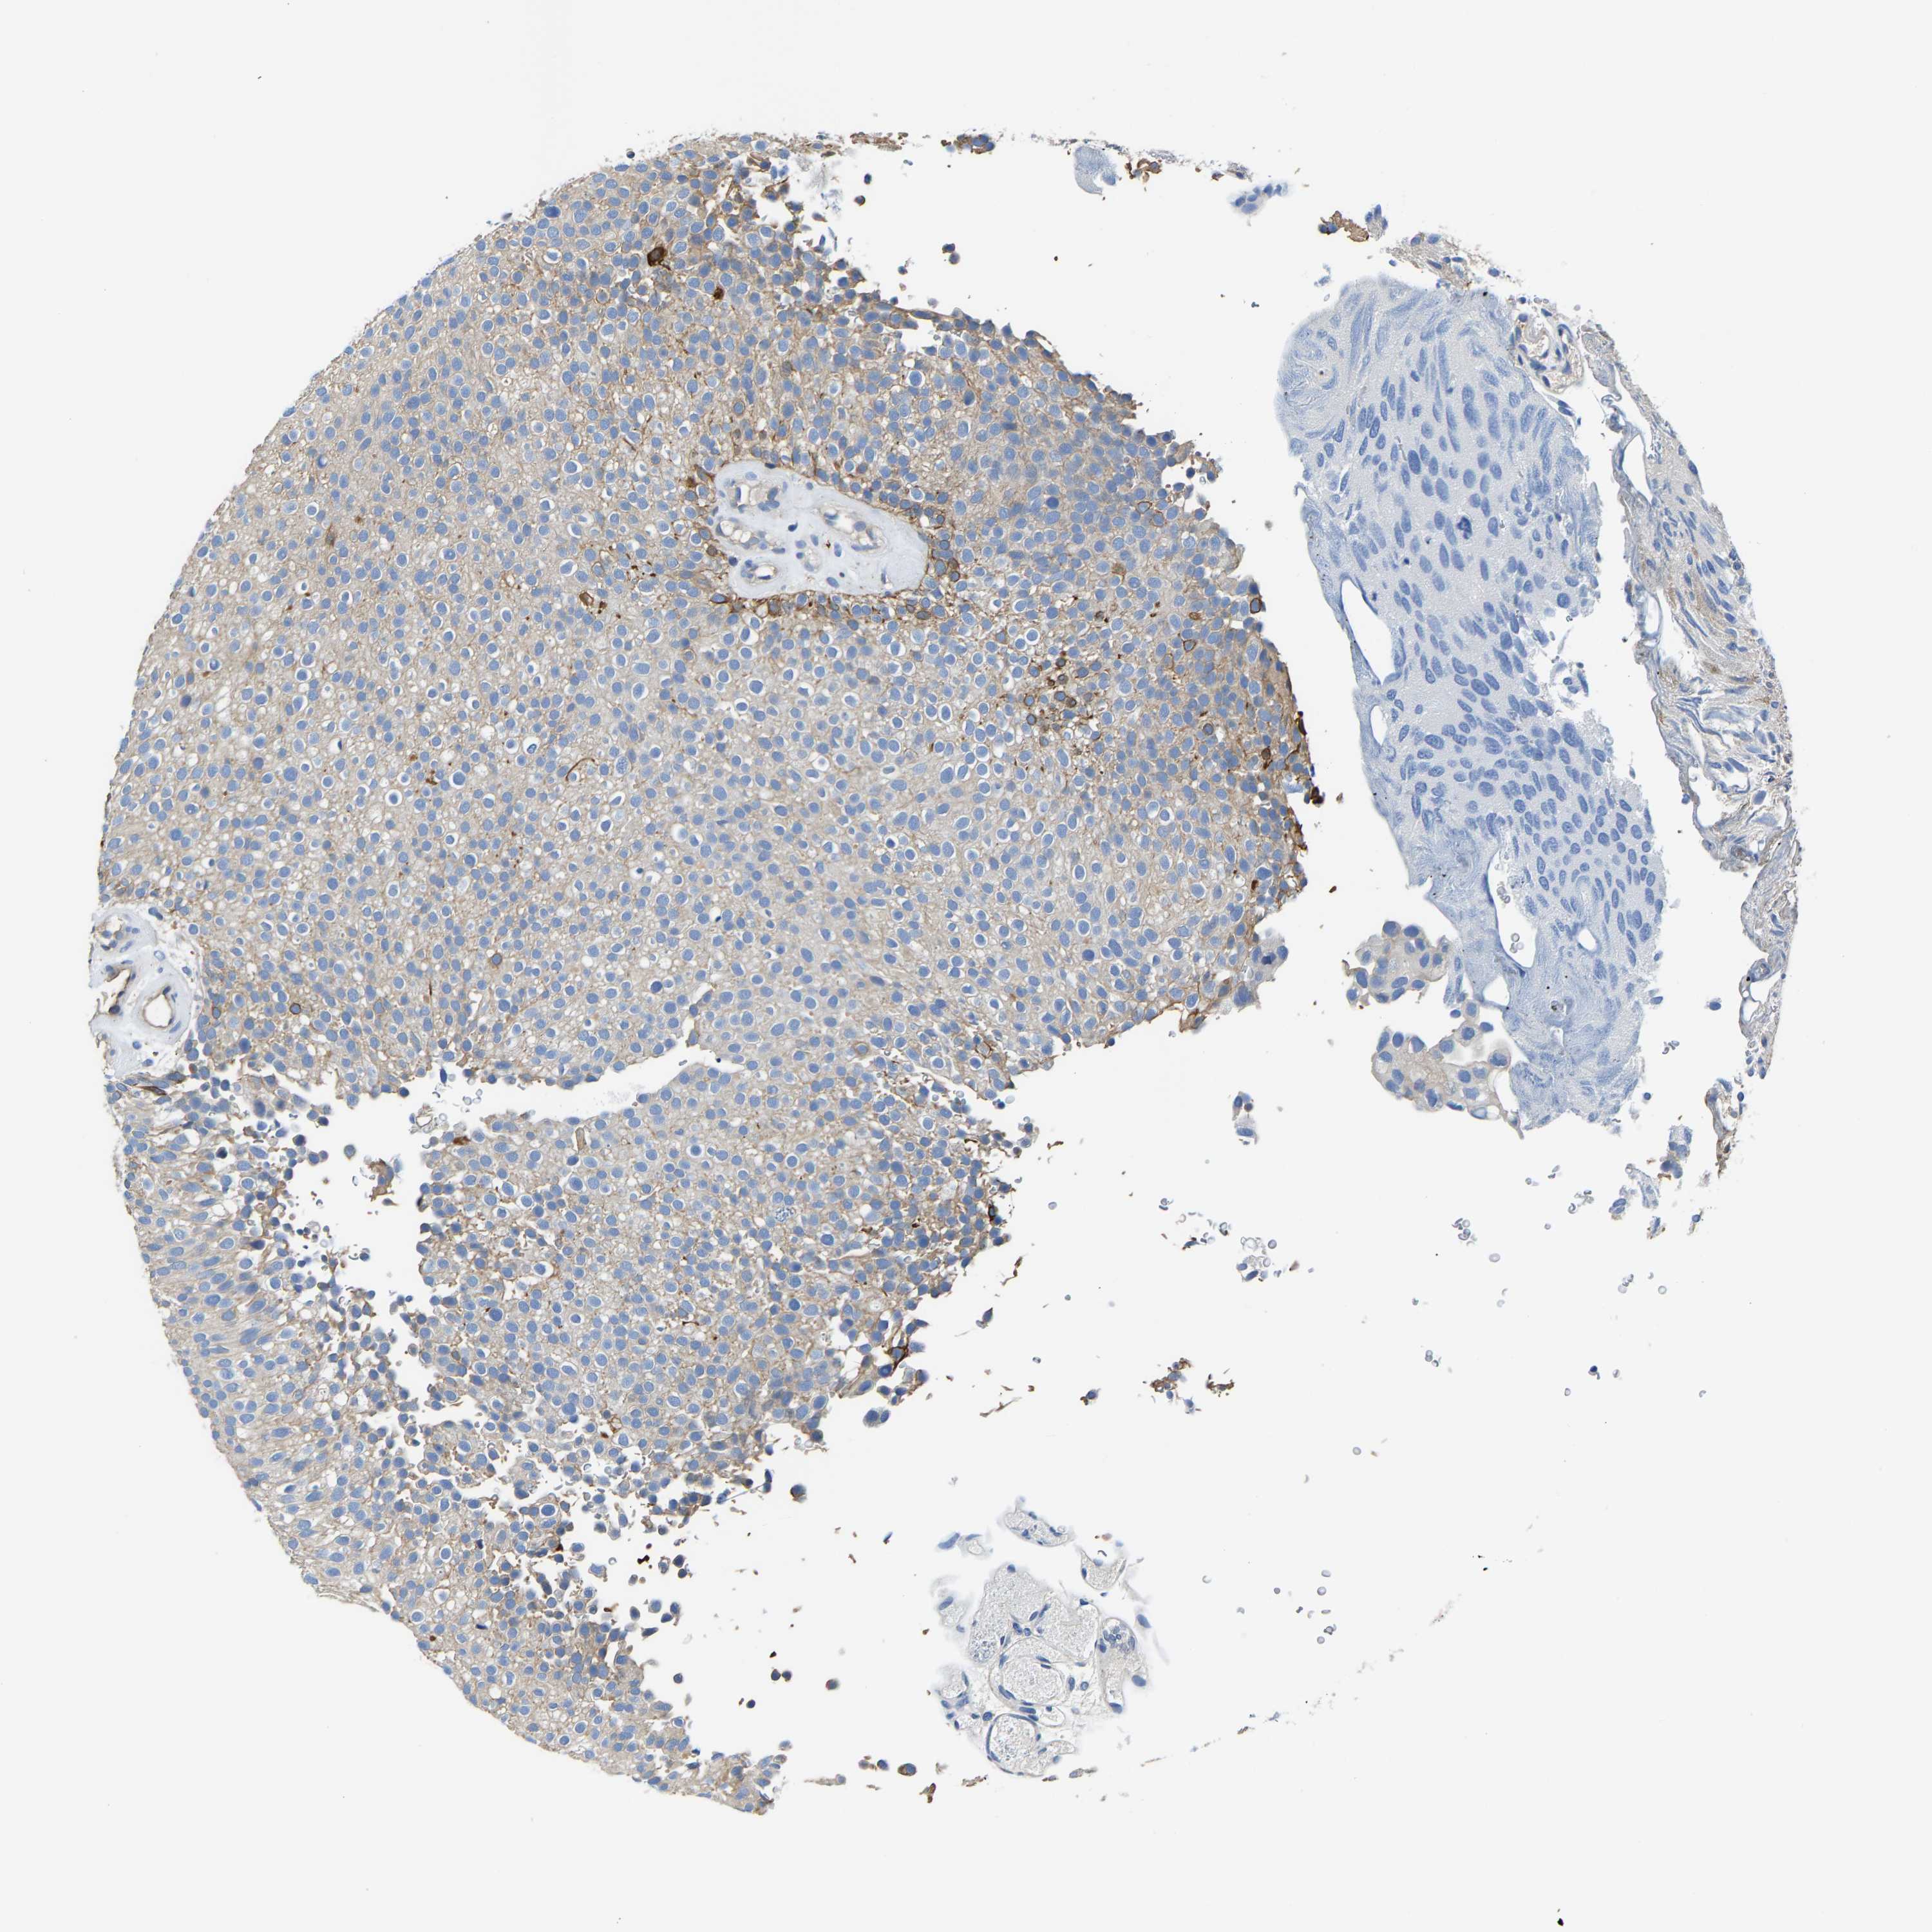

UROTHELIAL CANCER - Protein expressioni

A mouse-over function shows sample information and annotation data. Click on an image to view it in a full screen mode. Samples can be filtered based on level of antibody staining by selecting one or several of the following categories: high, medium, low and not detected. The assay and annotation is described here.

Note that samples used for immunohistochemistry by the Human Protein Atlas do not correspond to samples in the TCGA dataset.

Antibody stainingi

Antibody staining in the annotated cell types in the current human tissue is reported as not detected, low, medium, or high, based on conventional immunohistochemistry profiling in selected tissues. This score is based on the combination of the staining intensity and fraction of stained cells.

Each image is clickable and will lead to virtual microscopy that enables deeper exploration of all samples and also displays staining intensity scores, fraction scores and subcellular localization as well as patient and tissue information for each sample.

Antibody HPA019805

Antibody HPA020599

Antibody CAB004605

Staining

High

Medium

Low

Not detected

Intensity

Strong

Moderate

Weak

Negative

Quantity

>75%

75%-25%

<25%

None

Location

Nuclear

Cytoplasmic/membranous

Cytoplasmic/membranous,nuclear

Urothelial carcinoma, Low grade

Urothelial carcinoma, High grade